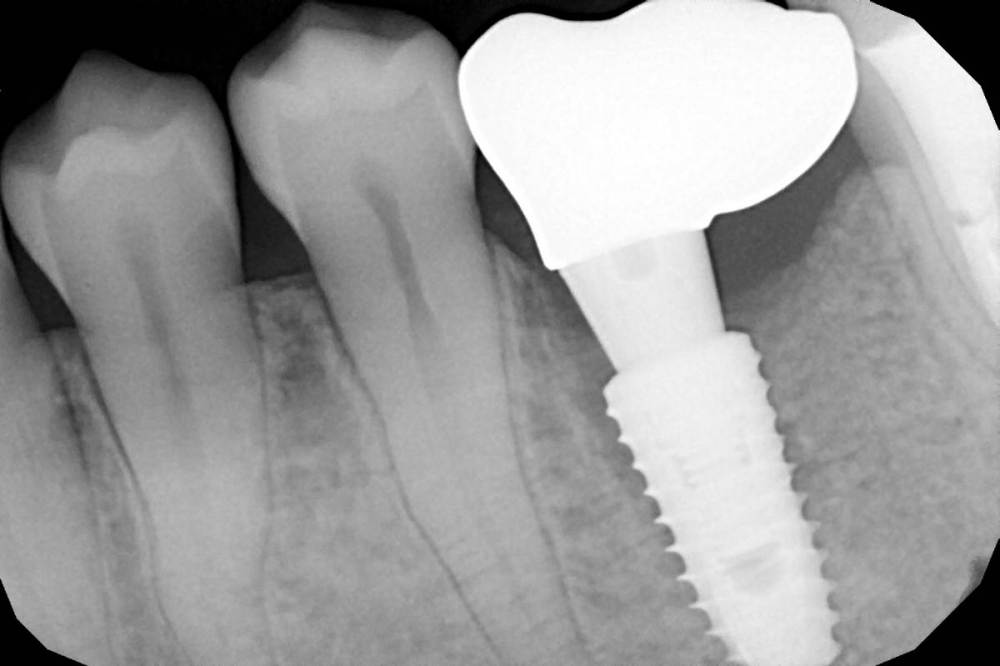

Женька Опубликовано 20 февраля, 2021 Поделиться Опубликовано 20 февраля, 2021 Коллеги, скажите пожалуйста кто что видит?Вчера заменил своему технику фдм с 4.5 на 5.5Через час отметил дискомфорт и легкие тянущие боли.Сегодня сказал, что болит, отдаёт в висок и ниже.Я по снимку не вижу что фдм в кость упёрся.При установке фдм пошире пац не отметил никаких ощущений, ну может лёгкий дискомфорт на последних оборотах.Фдм без особых усилий встал. Ссылка на комментарий

ilnurik Опубликовано 20 февраля, 2021 Поделиться Опубликовано 20 февраля, 2021 Да. Медиально придавил. 1 Ссылка на комментарий

Женька Опубликовано 20 февраля, 2021 Автор Поделиться Опубликовано 20 февраля, 2021 Да. Медиально придавил.Думаете это всё-таки кость? не десна? Ссылка на комментарий

ilnurik Опубликовано 20 февраля, 2021 Поделиться Опубликовано 20 февраля, 2021 Даже если десна, то она придавлена к кости. Поэтому такие ощущения Ссылка на комментарий

kramer Опубликовано 20 февраля, 2021 Поделиться Опубликовано 20 февраля, 2021 отдавить Должно быть пространство для отдавливания, а так выходит, что какой-то участок десны зажало между костью и фдм 3 Ссылка на комментарий

Женька Опубликовано 1 мая, 2021 Автор Поделиться Опубликовано 1 мая, 2021 Зафиксировали сегодня нашему технику циркон в полную анатомию... плюсом сажал сст одновременно и раздвинул десну язычно и вестибулярно. Зафиксировал без ишемии десны практически (немного побелела только). Что скажет по снимку, коллеги? 1 Ссылка на комментарий

Irouil Опубликовано 1 мая, 2021 Поделиться Опубликовано 1 мая, 2021 Какой техник технику коронку делал? Почему там зазор у основания?) Графтили под понтиком? Ссылка на комментарий

Женька Опубликовано 1 мая, 2021 Автор Поделиться Опубликовано 1 мая, 2021 (изменено) Техник сам себе коронку делал. Медиально зазор? Видимо потому, что при приклейке почему-то был люфт колпачка на абатменте... И мне этот момент непонятен, откуда этот люфт взялся. Под понтиком не графтил, там яма была вестибулярно в области понтика. Под понтиком полурасщепленный лоскут получился. И в этом месте циркон без глазури, только полировка. Щас модельку покажу. Изменено 1 мая, 2021 пользователем Женька Ссылка на комментарий

Irouil Опубликовано 2 мая, 2021 Поделиться Опубликовано 2 мая, 2021 (изменено) 5 часов назад, Женька сказал: @Irouil потому что не додумался заграфтить на этапе установки... Всё настолько хреново? Теперь Ваш графт может непрогнозируемо повлиять на уровень зенита и глубину эпителиального прикрепления. При этом высота основания/циркона/глазури Вами уже выбрана и их соотношение с биологическими потом может не совпасть. насчет «хреново» - я уже написал про медиальную сторону, с такой близостью костной поверхности зазор может оказаться критичным. Вы просто покажите технику снимок и спросите - его самого устраивает всё? Изменено 2 мая, 2021 пользователем Irouil Ссылка на комментарий

Irouil Опубликовано 3 мая, 2021 Поделиться Опубликовано 3 мая, 2021 Ну тогда пусть носит) на мой взгляд на этом снимке все видно без каких-либо специальных обучений - должно быть гладко, а торчит юбка. Ссылка на комментарий